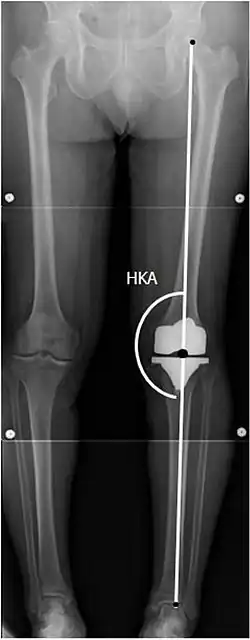

Knee replacement is routinely evaluated by X-ray, including the following measures:

![HKA: Hip-knee-ankle angle, which is ideally between 3° varum to 3° valgum from a right angle.[62]](./_assets_/X-ray_of_HKA_angle_with_knee_prosthesis.jpg)

- FFC: frontal femoral component angle. It is typically regarded as optimal when being 2–7° in valgus.[63]

- FTC: frontal tibial component angle, which is regarded as optimal when being at a right angle. A varus position of more than 3° has generally been found to increase the failure rate of the prosthesis.[63] -

- LTC: lateral (or sagittal) tibial component angle, which is ideally positioned so that the tibia is 0–7° flexed compared to at a right angle with the tibial plate.[63]